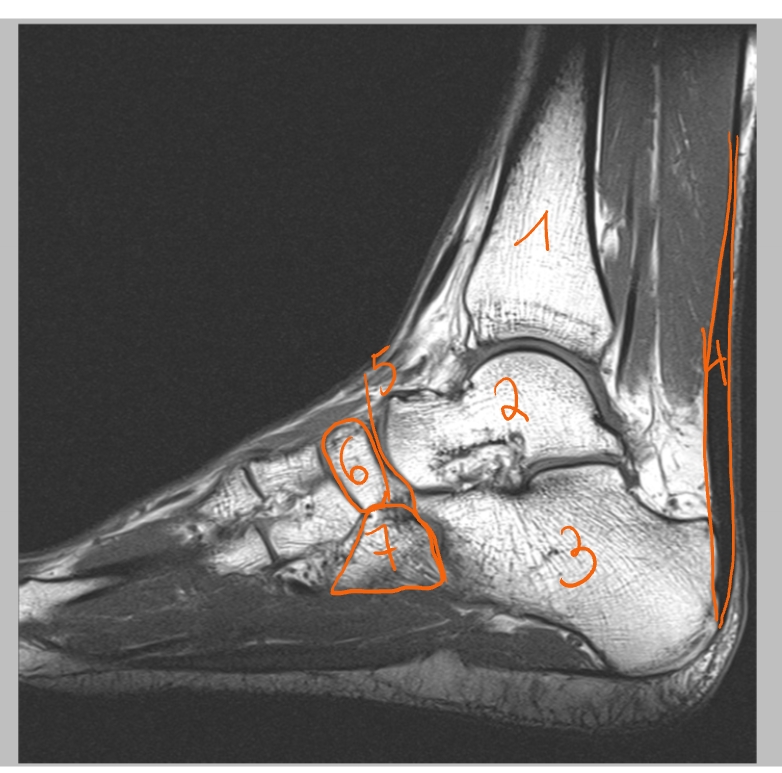

trochlea tibiae

talus

collum tali

caput tali

os naviculare

calcaneus

tuber calcanei

Achillespees → van m. triceps surae

malleolus medialis

Achillespees

gewrichtslijn van Chopart

os naviculare

os cuboideum

Achillespees

talus

os cuneiforme mediale

os cuboideum

os cuneiforme laterale